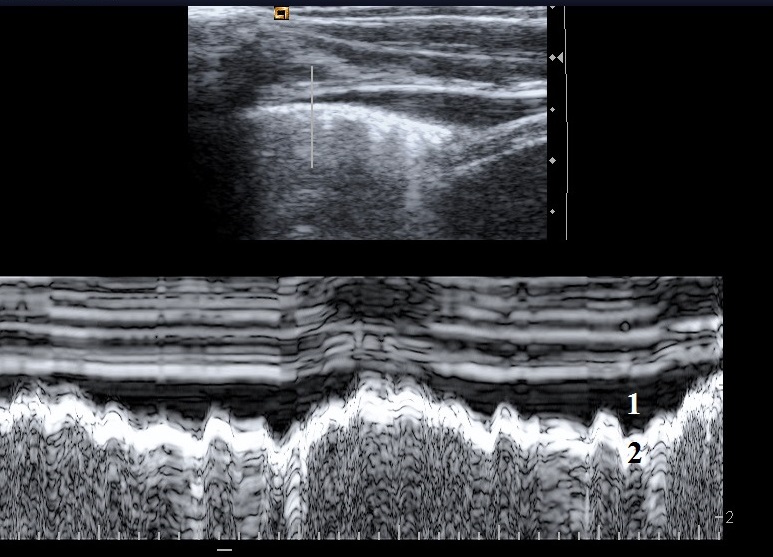

Enregistrement en mode TM (Time Mouvement) d’un autre épanchement pleural minime. Notez, là encore, la cinétique respiratoire de l’épanchement.

1 : épanchement pleural

2 : surface pulmonaire